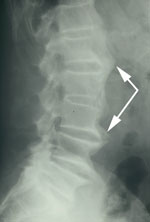

DISH generally affects at least 2 or more levels of the spine, and most often, 97% of cases, affects the thoracic spine.